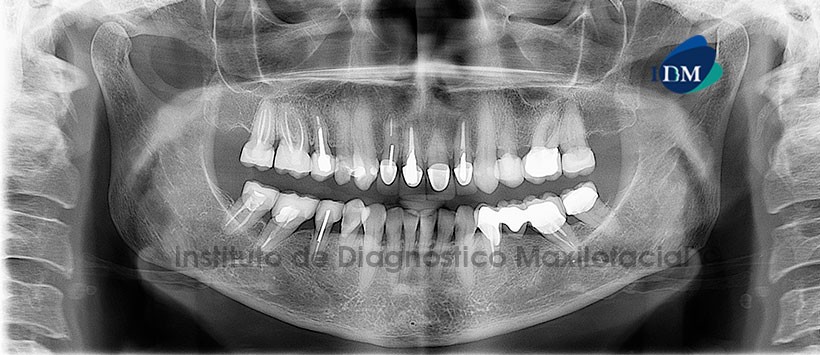

A la evaluación de la radiografía panorámica, se aprecia múltiples restauraciones con material de obturación de conductos y restauraciones protésicas, no se aprecia mayores hallazgos (Figura 1).

A la evaluación de la tomografía volumétrica (CBCT) en la reconstrucción panorámica de ATM (Figura2),  en cortes axiales (Figura 3), coronales (Figura 4) se observa alteración en la estructura y tamaño de la apófisis mastoidea donde apreciamos zonas hiperdensas que obliteran las celdillas mastoideas. En los cortes sagitales (Figura 5) se aprecia ademas espacios discales conservados.